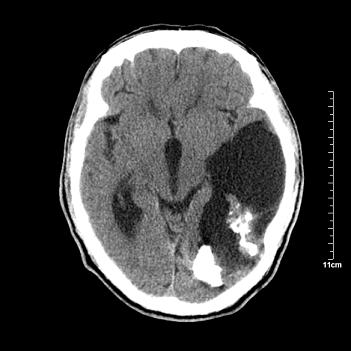

男性患者,72岁,近两天头晕来我院就诊。 因患者血压太高而未做增强,建议病人去市医院做mri检查。等得到mri随访结果再公布给大家。 测及左颞顶枕叶病灶ct值分别为5hu 30hu 729hu。

考虑左侧颞顶枕叶少突胶质细胞瘤。 今天随访患者手术病理结果 病理回报为胶质瘤2级 钙化

左侧颞顶枕叶巨大囊性病灶,灶内见小片实性区且灶内及灶周围大量团块状钙化影,灶周水肿少.左侧室枕角内见环形钙化,可见较清晰前壁,钙化与室壁似有间隙.

考虑1寄生虫病2表皮样囊肿钙化3血管畸形,其他不排

囊变明显,钙化明显,部分实性组织,轻度占位,左侧脑室受压---考虑 少突胶质细胞瘤,畸胎瘤,寄生虫病

今天追踪患者家属手术病理结果 病理回报为胶质瘤2级并钙化

病理回报为胶质瘤2级并钙化